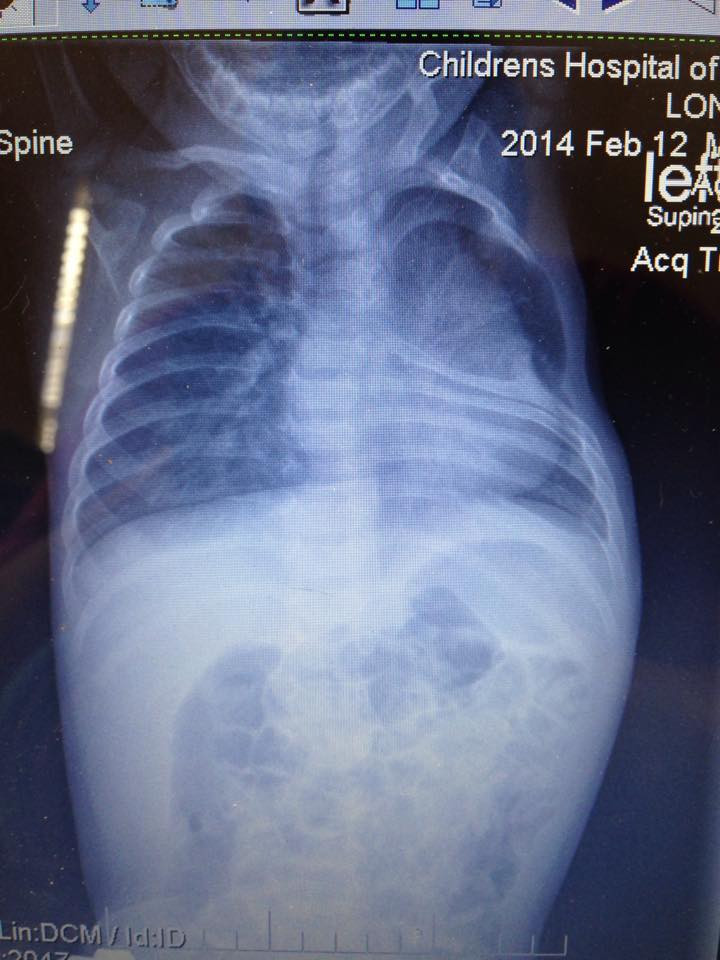

At 20 weeks gestation, we learned that I had a single umbilical artery and also that Ethan’s left kidney measured a little larger than normal. We met with a perinatologist and a genetic counselor and both thought all was well with Ethan despite the new findings. Around 26 weeks, I started having contractions and was put on bed rest. The medications and shots didn’t stop the contractions, so I had two rounds of steroid shots to help develop his lungs in case he came early. I think that because I was being monitored so closely since the contractions started, that’s the only reason they found “issues” with his spine, which was around 28 weeks. At this time, they told me that the kidney resolved and was now normal in size and the ultrasound tech talked with the perinatologist about the spine and he wasn’t concerned. Two weeks later when they saw it again, they ordered a fetal MRI, which showed nothing. Around 33 weeks I saw the perinatologist to discuss MRI results and he took a really good look at the spine and said that he suspected hemivertebrae and missing ribs, but we would just have to wait it out until Ethan was born, but assured me that this wasn’t something to be concerned about….I was very concerned.At 39 weeks 4 days, Ethan was born. He didn’t require anything special, no oxygen, we went to a normal room, he was doing wonderfully, just breathing faster than normal. They didn’t run any tests until a few days later, but we learned that he was missing his left 4th rib, had 4 abnormal ribs above and below the missing rib, had congenital scoliosis and his left kidney was still dilated. At discharge, they set us up with orthopedics and a geneticist, which we saw soon after we were discharged. The geneticist told us that he didn’t feel it was a syndrome, but more so from the two vessel cord and not enough blood flow to the area during development. Orthopedics evaluated him, took an x-ray and said all was well and to come back in a year. This is where something in my gut told me something wasn’t right…a whole year? We saw pulmonology when Ethan was 3 months old and he just said that Ethan may need a surgery when older for his pectus excavatum (sunken chest) but it would be cosmetic.

Again, something wasn’t sitting right with me. At this point, Ethan was holding his head up well and when I held him under his arms, I could feel that his shoulder blade was high in his neck and I couldn’t feel the bottom of it. I got on the internet and looked up doctors who specialize in chest wall deformities, San Antonio and Children’s Hospital of Philadelphia (CHOP) seemed to be leading hospitals with this expertise. I sent Ethan’s records right away so the doctors at each hospital could look over them and get back to me. We live in New Mexico, so I wanted to make sure a trip for a second opinion was warranted. Both San Antonio and Philadelphia thought Ethan would need a VEPTR (vertical expandable prosthetic titanium rib) and that we needed to schedule and evaluation. The VEPTR helps children with scoliosis to the point where it is affecting their lung function. The device can be placed rib to rib, rib to spine or rib to pelvis. It helps expand the ribcage, giving the child room to breathe, while helping maintain the curve in the spine.

We went to Philadelphia for the first time in August of 2014, Ethan was 6 months old. We met with an orthopedic surgeon, a thoracic surgeon, a pulmonologist, nutritionist, physical therapy and had x-rays, MRI’s and a CT scan. This is when we found out that Ethan has a partial fusion at T2-3 and T4-5 and a butterfly hemivertebrae at T2. We also learned that his left lung was only able to inflate to 60ml’s, where the right lung was 211ml’s. And, that his left shoulder blade had dropped into his chest cavity where the missing rib is and was attached to his lung, preventing it from expanding. Because of this, our surgeon wanted to do the surgery ASAP, as he thought it would benefit Ethan since it was already greatly involving lung function. The surgeon said that if it weren’t for the shoulder blade being in the chest cavity, we would have waited it out. We had to get weight on Ethan for the surgery, because he breathed so fast, he burned calories much faster than he should have. Surgery was scheduled for 3 months later.